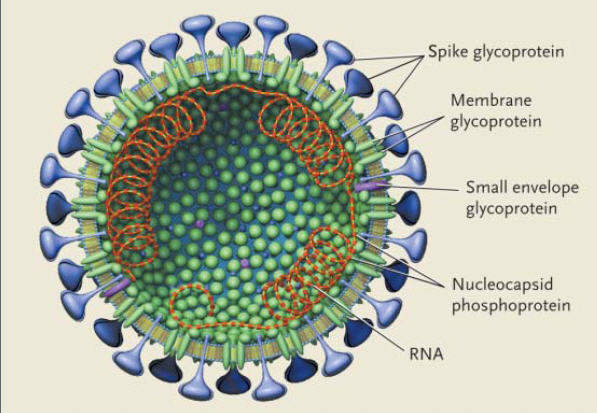

2003年3月

SARS爆发,最终在29个国家出现了8100个病例,至少导致774人死亡。